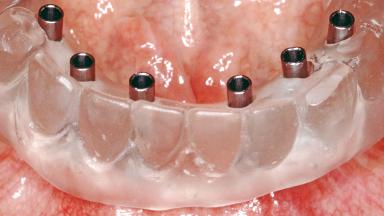

Conventional Loading of Six Implants in the Mandible and Final Restoration with a Full-Arch Metal-Ceramic FDP

A 68-year-old, completely edentulous male patient presented for evaluation and treatment options. He reported excellent general health and was taking no regular medication. He had been edentulous for approximately 12 years, having lost his teeth to periodontal disease and dental caries. The patient’s chief complaint was incompetent function. His secondary concerns included his appearance and the desire for a predictable outcome. He attributed his reduced functional capacity to his lower complete denture, which he described as poor. He was particularly concerned with the denture’s instability and poor fit. In general terms, he was satisfied with the maxillary complete prosthesis. The maxillary prosthesis was characterized by adequate retention, stability, and support, although the fit was considered less than ideal.

# of Implants 6

Type of Implants One-Piece

Defining Characteristics Fully edentulous lower jaw to be rehabilitated with an implant-borne fixed dental prosthesis

Loading Protocol Conventional/early

Retention Screw-retained, with 4 or more splinted implants Screw-retained, with 4 or more splinted implants